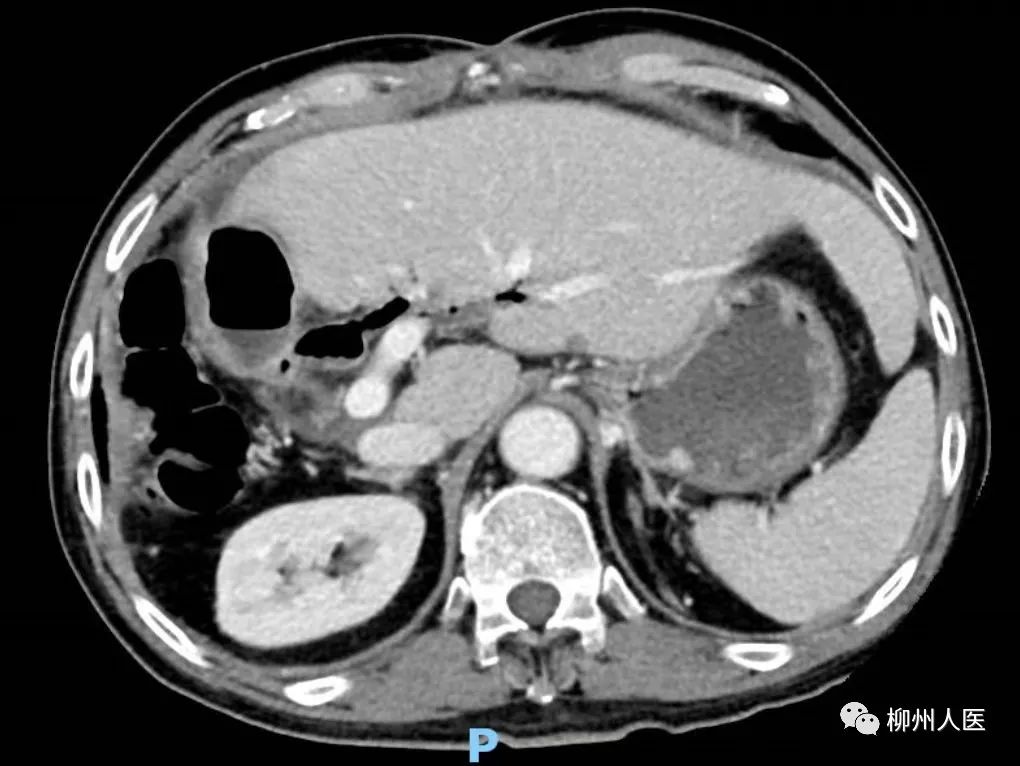

▲第二次手術前

一月后李阿公再次返院治療,經再次評估達到二次肝切除手術的安全標準。綜合外科肝膽病區團隊再次手術,沿著瘤體 “抽絲剝繭”,最終完整切除腫瘤。術后,在快速康復外科(ERAS)理念及措施的支持下,李阿公順利出院。